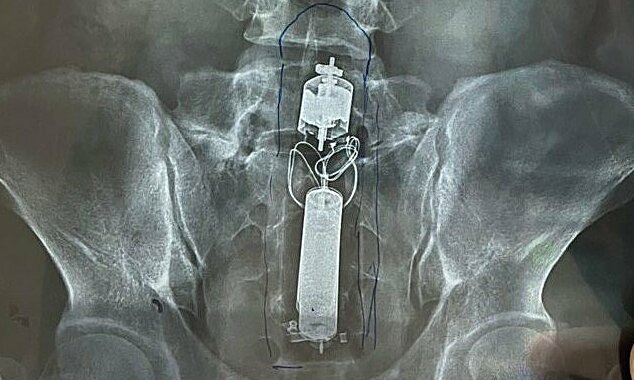

Hình ảnh chụp X-quang đã phát hiện dị vật trong trực tràng của bệnh nhân. Ảnh do bệnh viện cung cấp.